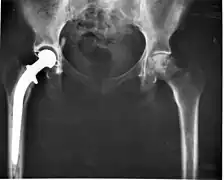

Head of the hip bone.